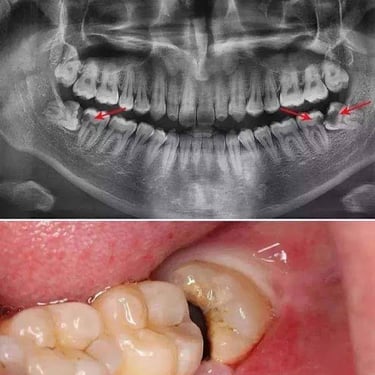

Extracción de Muelas del Juicio

La extracción de las muelas del juicio es un procedimiento quirúrgico para remover los terceros molares que pueden causar dolor, infección o daño a otros dientes debido a su posición o crecimiento anómalo.

Los pacientes pueden experimentar dolor, hinchazón y, en algunos casos, infección alrededor de estas muelas.

El tratamiento incluye la extracción quirúrgica para prevenir o resolver complicaciones.